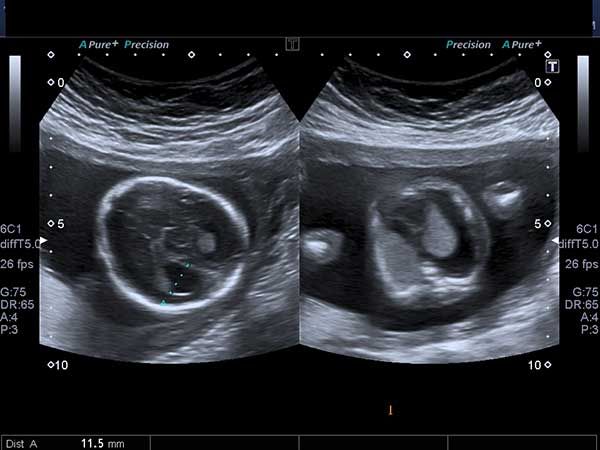

To better balance the use of ultrasound and the time needed to ensure that an early pregnancy is not incorrectly declared nonviable, a group of experts have introduced new diagnostic thresholds.

A 40-year-old woman reports a 20-week history of amenorrhea. What is your diagnosis based on these images?

What is your diagnosis of this incidental finding during routine ultrasonography in a 15-week fetus?